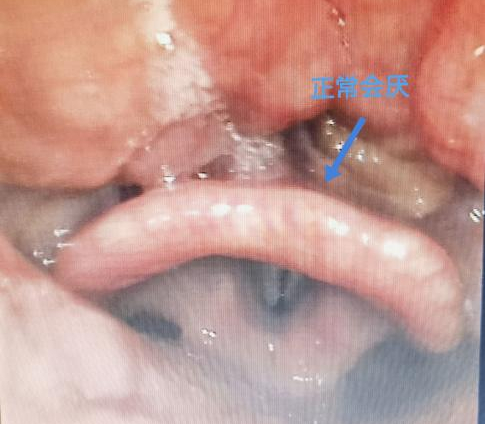

会厌是我们咽喉部结构的一部分,正常的会厌形态像一片“小叶子”,附着在舌根后部,张开嘴巴或压舌头较难以观察,需要借助喉镜才能完全查看。

李永贺主任介绍,会厌就在气道上方,当会厌因感染、损伤、过敏等各种因素导致炎症反应时,会出现局部水肿变形,从一片“小叶子”变成肿胀的“气球”,直接堵住呼吸通道,继而引起窒息。